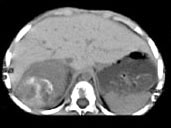

- 多项选择题男,5 岁, 消瘦、贫血、纳差和腹部包块3个月,CT检查如图, 下列说法正确的是  (    )

- A、右侧腹腔内可见一巨大软组织肿块影,其边界欠清楚

- B、肿块密度不均匀,可见片状的较高密度,考虑为出血,也可见点状的钙化影

- C、该病灶来源于肝脏,考虑为肝母细胞瘤

- D、该病灶来源于右肾上腺,考虑为神经母细胞瘤

- E、该病灶来源于右肾,考虑为肾胚胎瘤